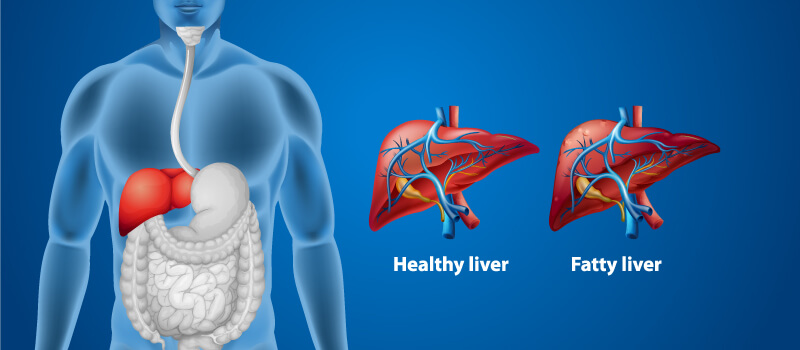

آیا می دانستید کبد که در قسمت راست بدن و بالای شکم قرار دارد، بزرگترین اندام داخلی بدن نیز به شمار می آید؟ و در صورت رعایت نکردن برخی مسائل، مشکلاتی به همان اندازه بزرگ، برای شما به وجود می آورد؟ کبد چرب یکی از شایع ترین مشکلات این عضو بدن است. بنابراین آگاهی از اینکه علائم کبد چرب چیست و چگونه درمان می شود، لازم و ضروری به نظر می رسد.

قبل از به جریان افتادن خون از دستگاه گوارش، این کبد است که خون تقویت شده را به همه قسمت های بدن ارسال کرده و به عنوان فیلتر بدن عمل می کند، اما این فیلتر زمانی به مشکل می خورد که چربی آن به بیش از حد مجاز برسد و به اصطلاح کبد، چرب شود. اگر به دنبال علت چرب شدن کبد به همراه راه های درمان آن هستید و می خواهید اطلاعات خود را در زمینه کبد افزایش دهید، با ما در این مقاله همراه باشید.

بیماری کبد چرب توسط جمع شدن نوعی چربی اضافی در سلول های کبدی به وجود می آید که می تواند در برخی کشورها از معضلات سلامت جامعه باشد. بر اساس مطالعات در کشورهای غربی و اروپایی به طور میانگین از هر 10 نفر، یک نفر مبتلا به کبد چرب است. این مسئله که کبد مقدار مشخصی چربی دارد، بسیار طبیعی است، ولی مشکل از جایی شروع می شود که این چربی به بیش از 10 درصد می رسد. این به آن معنا است که اگر درصد چربی در کبد شما بیش از 10 درصد است، شما دارای یک کبد چرب هستید که ممکن است عوارض جدی تری به همراه داشته باشد! جهت آگاهی از علائم کبد چرب و علت آن، ادامه مطلب را از دست ندهید.

کبد چرب چه مشکلاتی ایجاد می کند؟

لازم است بدانید که چرب شدن کبد همیشه باعث ایجاد آسیب نمی شود، اما در مواقع دیگر کبد می تواند دچار التهاب شود. این بیماری که استئاتو هپاتیت نام دارد، نوعی از آسیب دیدگی های کبدی به حساب می آید که گاهی با سوء مصرف الکل ارتباط دارد و به عنوان استئاتو هپاتیت الکلی شناخته می شود؛ در غیر این صورت این بیماری را NASH یا استئاتو هپاتیت غیر الکلی می گویند. کبد ملتهب ممکن است به مرور زمان باعث سفت شدن یا زخمی شدن شود. این وضعیت سیروز کبدی نام دارد و باید آن را جدی گرفت، چرا که در اغلب اوقات رسیدگی نکردن به آن منجر به نارسایی کبدی می شود. NASH یا استئاتو هپاتیت غیر الکلی، یکی از علت های اصلی سیروز است.